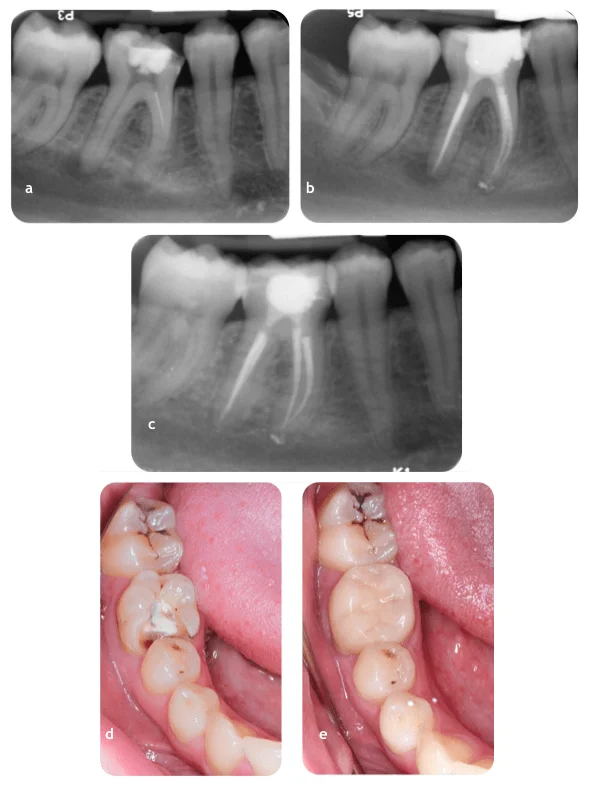

Case 2

Review of tooth 46 (a) Pre-operative radiograph (b) Postoperative radiograph (c) 1-year review radiograph (d) Pre-operative photograph (e) Postoperative photograph.